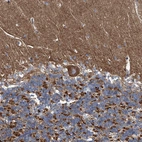

Immunohistochemical staining of human cerebellum shows strong cytoplasmic positivity in Purkinje cells.